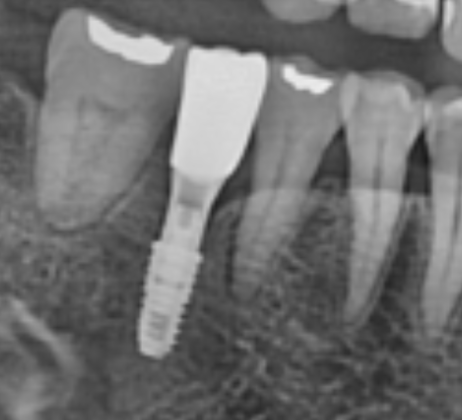

위 사진처럼 1개의 임플란트로 2개 치아 역할을 할 수 있습니다. 아래쪽 앞니의 모습인데요.

아래쪽 앞니는 우리의 치아들 중에서도, 폭이 가장 좁은 곳입니다. 그래서 치아가 2개가 빠져도, 2개를 심기 어려운 경우가 많아서.. 1개만 심고 위 사진처럼 보철을 추가하는 경우도 있습니다.